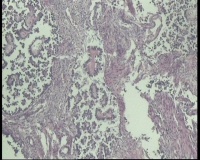

| 性别 | 女 | 年龄 | 53岁 | 临床诊断 | 右侧卵巢囊肿 |

| 一般病史 | 彩超:盆腔可见囊实性回声,囊性为主,大小约5.0x3.7厘米,其内可见分隔回声,部分分隔内回声不纯净,形态欠规整 | ||||

| 标本名称 | 腔镜下右侧卵巢囊肿手术 | ||||

| 大体所见 | 囊壁样组织5.5x5.0厘米,4.5x2.5厘米2块,壁厚0.1-0.2lm,囊壁大部分光滑,局灶见0.7x0.5x0.3厘米淡黄色突起组织,另见淡黄色、肉粉色质软组织2.8厘米一堆。 | ||||